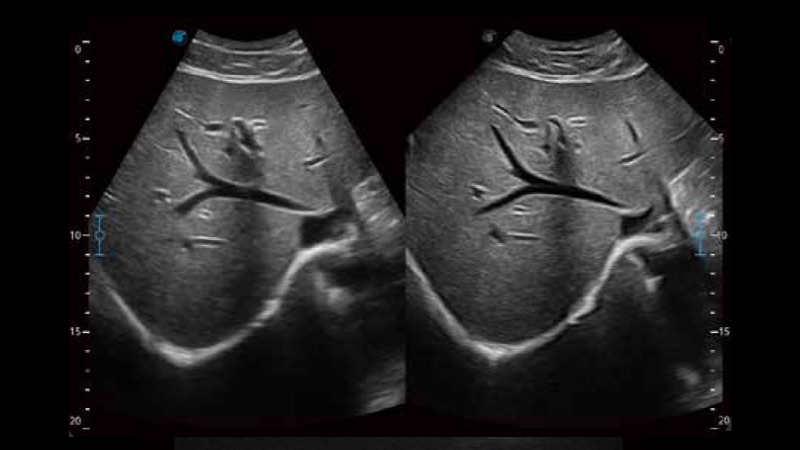

开立医疗通过不断的技术创新,为大众的生命健康提供持续关爱。P12 Plus采用全新一代超声成像平台,新平台旨在将真实还原组织解剖结构作为首要目标。平台采用全新集成化硬件模块,搭载新一代芯片,系统性能得到大幅提升,为您的诊断提供了丰富的临床信息。优异的图像表现,丰富的探头配置,全面的应用功能,为您日常诊断提供了可靠的助手。

凭借开立医疗先进的成像技术和优异的探头技术提供的清晰的图像表现,您可以更自信地做出临床决策。